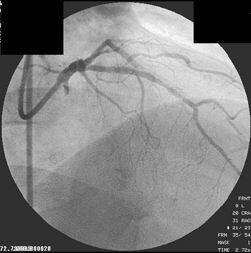

S670を植え込んだほぼ1年後に、血栓性の閉塞を来したAMI症例を経験したこと

画像のPCI-1、2、3は1stPCIで1年後のAMI、resque後、stenting後となっています。

resqueでは血栓が引けたように記憶しています。